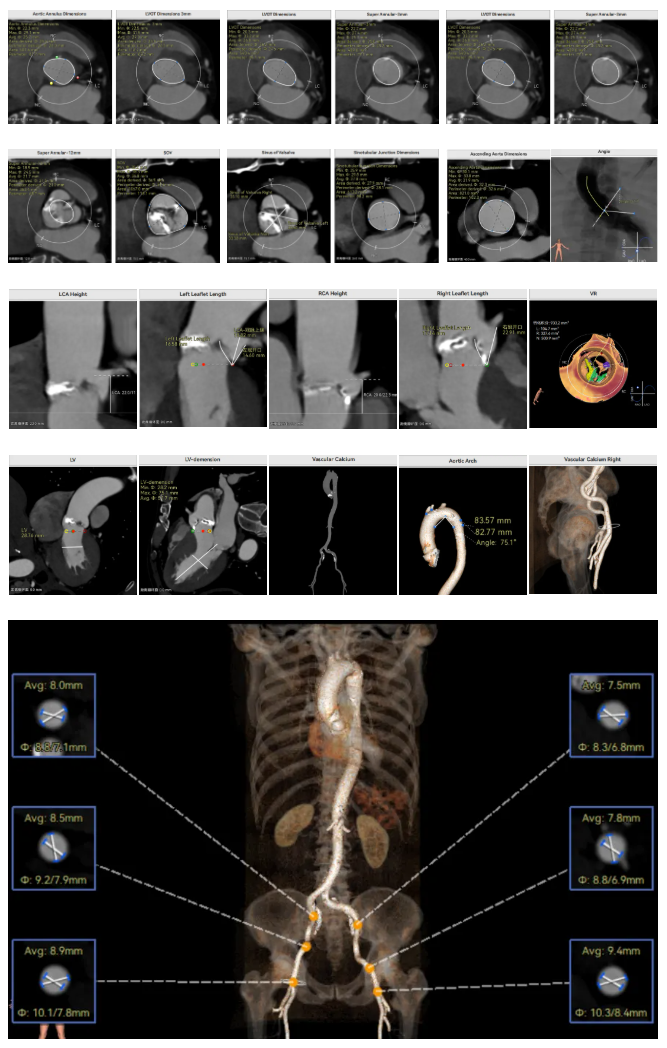

李有金教授 宁夏回族自治区人民医院 “随着人口老龄化加剧,主动脉瓣狭窄患者数量逐年增多,其中高龄、合并多种基础疾病的复杂病例占比不断提升。经导管主动脉瓣置换术(TAVR)作为微创治疗技术,已成为此类患者的重要治疗选择。对于高龄、有恶性肿瘤病史的患者而言,手术的安全性、微创性与长期疗效同等重要,既要最大程度降低手术创伤与并发症风险,也要确保瓣膜的耐用性与患者术后生活质量。 全球首款预装干瓣ProStyle A®的临床应用,为复杂病例治疗提供了全新解决方案。该瓣膜无需术中戊二醛冲洗,大幅缩短了手术操作时间,尤其适合高龄、心功能欠佳的患者。其独特的抗钙化工艺与优化的瓣架设计,既保证了瓣膜的长期耐久性,又能有效规避冠脉风险,为患者的“全生命周期管理”奠定了坚实基础。” 病例简介 现病史:患者半月余前突发抬头时一过性头晕,持续数秒钟,每日发作3-5 次,伴天旋地转感,症状可自行缓解。2025年12月12日就诊于外医院,心脏彩超提示“主动脉瓣狭窄(重度)并关闭不全(轻度),左室壁增厚,升主动脉增宽,左心室收缩功能正常,舒张功能减退”,建议转上级医院诊治。为求进一步治疗,患者就诊我院,门诊以“主动脉瓣狭窄”收住入院。 既往史:胃癌,胃大部切除术后五年。 临床诊断:“1.主动脉瓣狭窄伴有关闭不全(重度狭窄伴轻度关闭不全);2.主动脉瓣钙化;3.肥厚性非梗阻性心肌病;4.心功能不全;心功能III级(NYHA分级);5.升主动脉扩张;6.胃恶性肿瘤个人史” 术前CT评估显示:Type-1型二叶瓣,R-N钙化粘连,瓣叶重度钙化,主要分布在无冠窦瓣叶游离缘、R-N对合缘粘连处及右冠窦基底部;钙化积分933.2mm³;主动脉瓣环直径26mm,LVOT 27.6mm;双侧瓣叶开口高度可,左冠开口高度22.0mm,右冠开口高度20.0mm;主动脉水平夹角57.7°,左室内径偏小;主动脉弓部75.1°锐角弓;外周入路无明显迂曲及钙化,双侧股动脉内径可,右股中分叉。 手术策略 右侧股动脉为主入路,左侧为辅助入路,20F大鞘,股骨头中段穿刺;预装金仕生物 ProStyle A® AV26瓣膜,备29瓣膜,22mm球囊预扩;初始定位对齐瓣环上5mm超高位释放,释放过程中使瓣膜自然下滑至工作位,最终理想位置零位,利用瓣上锚定与封堵,规避冠脉风险;术前适当补液; 手术过程 Step1:主动脉根部造影; 主动脉根部造影 Step2:使用“先瑞达”22mm球囊预扩,无腰无漏,冠脉充盈良好; 球囊预扩 Step3:将ProStyle A®预装干瓣送至目标位置,初始定位后缓慢释放,观察瓣膜自然下滑至理想工作位; 定位 释放至工作位观察 Step5:瓣膜完全释放后,再次造影,显示瓣膜位置、形态良好,导管测平均跨瓣压差由术前60mmHg-降至1mmHg,冠脉血供正常; 最终造影 Step6:术后即刻超声监测,人工瓣膜位置固定,瓣叶启闭无受限,瓣周少量反流。 术后患者病情稳定,已于一周后出院。 结语 作为宁夏回族自治区心血管疾病诊疗的核心高地与区域医疗中心建设的标杆单位,宁夏回族自治区人民医院始终坚守“敬佑生命、救死扶伤”的医者初心,以“技术引领、学科兴院”为发展理念,在心脏大血管领域持续深耕,构建了集“精准评估-个性化方案-微创治疗-全程康复”于一体的诊疗体系。此次西北首例ProStyle A®预装干瓣植入手术的圆满成功,不仅是医院在复杂结构性心脏病介入治疗领域的又一突破性成果,更彰显了医院在引进前沿技术、转化创新器械、服务复杂重症患者方面的责任与担当。 Prostyle A®预装干瓣——助力临床最优化解决方案: 预装干瓣 便捷顺安:金仕生物专利抗钙化技术运用纳米技术去除组织内的细胞碎片和磷脂,封闭游离醛基,从根本上阻断了瓣膜钙化的多项因素,显著提升了瓣膜的耐久性;同时,相比较传统戊二醛保存方式,干式存储最大限度的保留心包的亲水亲油平衡,还原组织天然曲柔性,进一步保障了瓣叶开合,保证长期耐久性; 平衡径向支撑力:Prostyle A®瓣架网孔比例按照病例解剖结构的特殊设计,使瓣膜在狭窄最重的地方良好的撑开,同时避免对瓣环及周边组织的过度压迫,有效降低传导阻滞风险; 精准释放:底部桶状设计更易迅速锚定,协同释放张力小,助力最终精准释放; 过弓柔顺:较细的输送系统直径+亲水涂层,显著提升输送系统通过性,有效减少血管并发症的发生,内连鞘版本最小尺寸等效14F大鞘; 专家简介 李有金 宁夏回族自治区人民医院(点击查看专家详细简历) · END ·